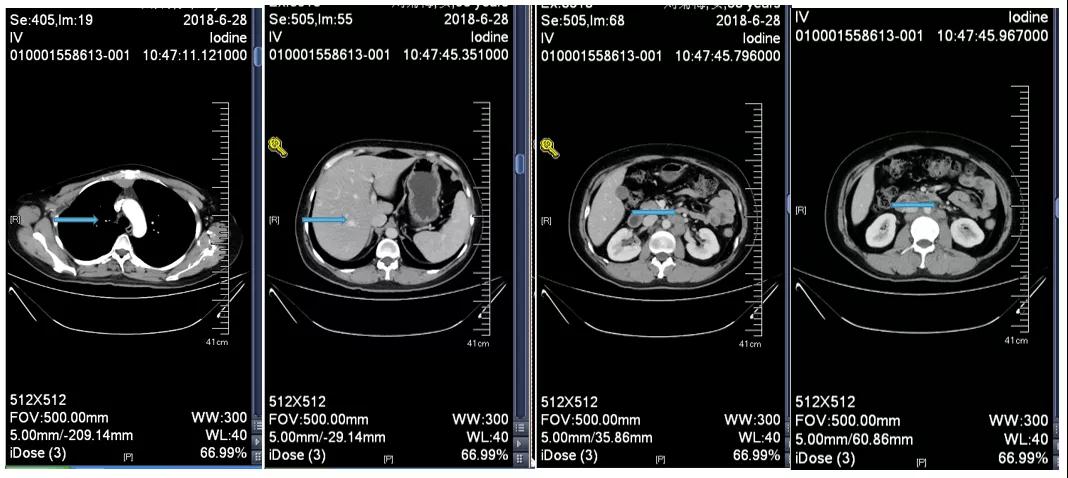

胸腹部增强CT示(2018-6-28):胸骨后占位,肝内异常强化灶,腹膜后肿大淋巴结。

靶病灶:腹主动脉左侧和下腔静脉右侧淋巴结

非靶病灶:肝左叶、肝右前叶下段;纵膈胸骨后淋巴结节;前上纵膈淋巴结;腹膜后小淋巴结

影像学评估-纵膈淋巴结: